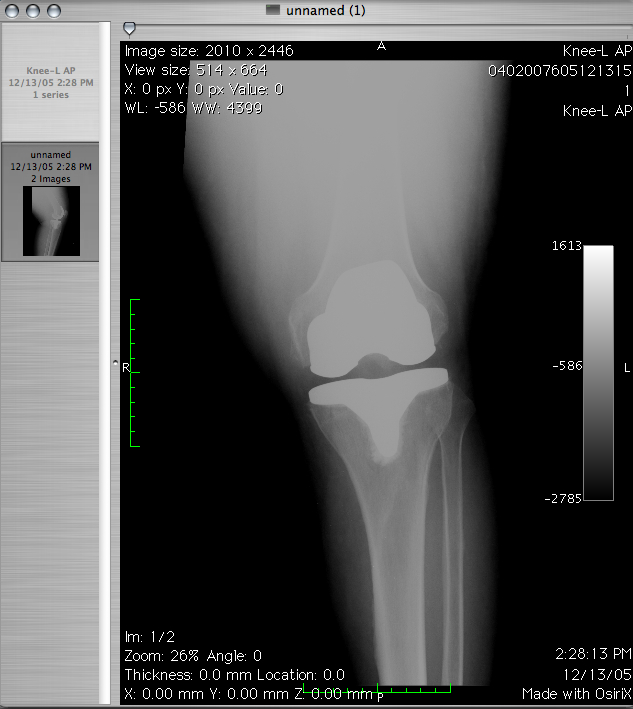

Rehabilitacja to dziedzina medycyny, która bardzo szybko się rozwija. Nie wiedzieliśmy kiedyś jak wielki potencjał …

Rehabilitacja obecnie rozwija się niezwykle szybko. Dawniej nie wiedzieliśmy, jaka moc w niej drzemie. Obecnie …

Jedną z szybciej rozwijających się dziedzin jest rehabilitacja. Niegdyś była ona niedoceniana. Obecnie wykorzystujemy ją …

Jedną z szybciej rozwijających się dziedzin jest rehabilitacja. Nie wiedzieliśmy kiedyś jak wielki potencjał w …